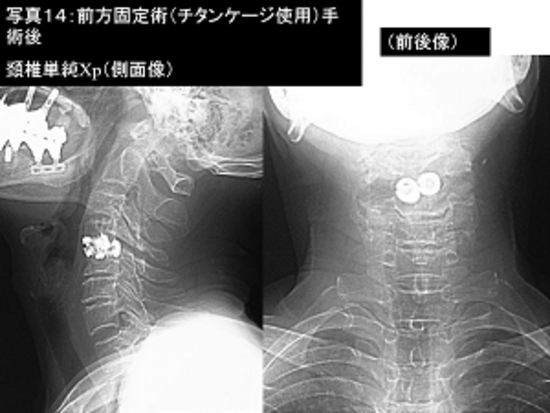

写真14:写真13の患者さんの手術後の頚椎単純レントゲン撮影像です。